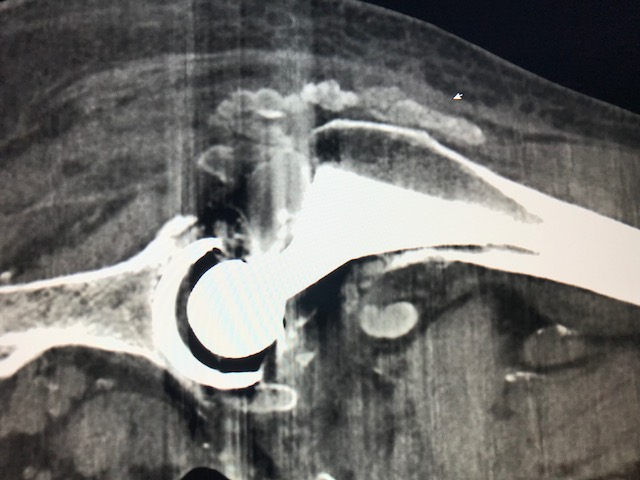

Figure 1 for case Tumoral calcinosis ( RID5202 )

Figure 1